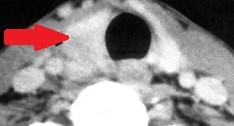

Contrast-enhanced CT demonstrates soft-tissue lesion in left carotid sheath (Courtesy Dr. V. Penopoulos)